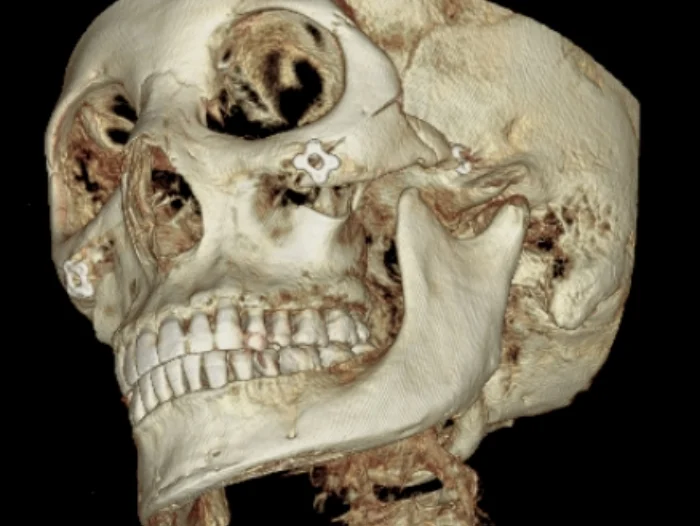

可以清楚確認嵌入在下顎與顴骨部位的金屬固定釘。

- 全方位影像判讀:身為少數擁有 3D CT 的皮膚醫療機構,我們能精確掌握脂肪、肌肉分佈以及金屬固定釘的具體位置

透過 CT 掃描精確確認金屬固定釘位置